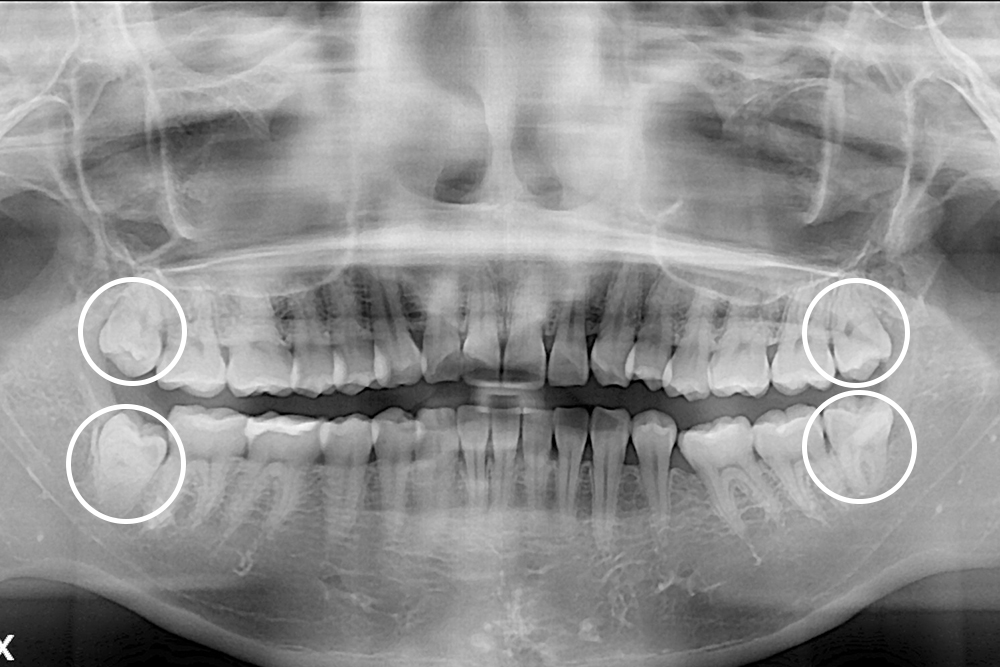

[사랑니] 매복 사랑니 발치

치료전 : 2021-02-18